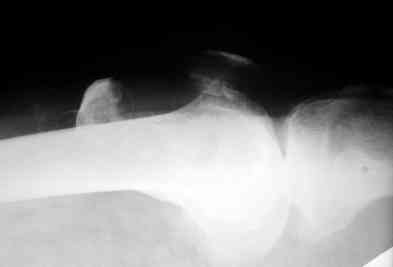

прилагаю снимки надколенника.

po moemu na snimke viden avascul necrosis of talar bone . lechit v cootvetstvii .

Надо "трогать". Подтаранный артродез очень показан и синтез перелома так же.